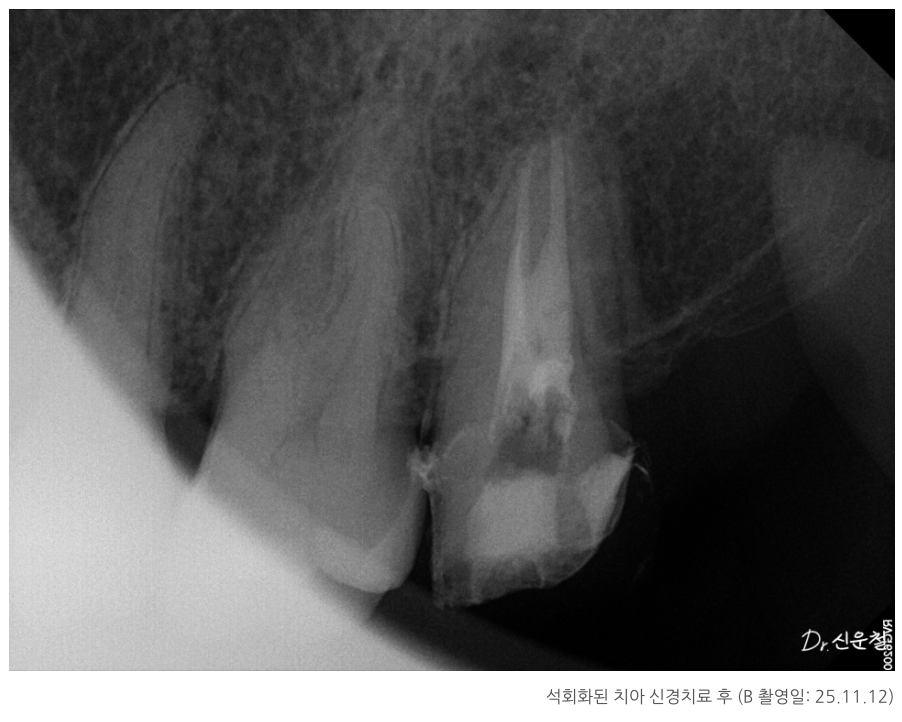

석회화된 치아, 정말 방법이 없을까?

실제 내원 사례 중에는

이미 신경치료를 받은 어금니에서

잇몸이 다시 붓고 고름이 차

발치 진단을 받고 오신 분도 계셨습니다.

또 다른 분은

“신경치료가 어렵다”는 설명을 듣고

의뢰로 내원하신 경우였습니다.

이 치아의 특징은 치아 안쪽 신경이 지나가는 길이

오랜 시간에 걸쳐 점점 막혀 있던 상태,

즉 석회화였습니다.

중요한 건 ‘과거 치료’가 아니라 ‘지금 상태’

이 두 경우 모두에서

치료 시작 전 가장 중요했던 기준은

과거에 어떤 치료를 받았는지가 아니라,

- 지금 이 치아 안쪽에 다시 접근할 수 있는 여지가 있는지였습니다.

치아 안쪽을 직접 확인하면서

남아 있는 길이 있는지

다시 정리가 가능한 상태인지 를 기준으로 판단했고, 그 결과

두 경우 모두 발치 대신 신경치료를 진행할 수 있었습니다.